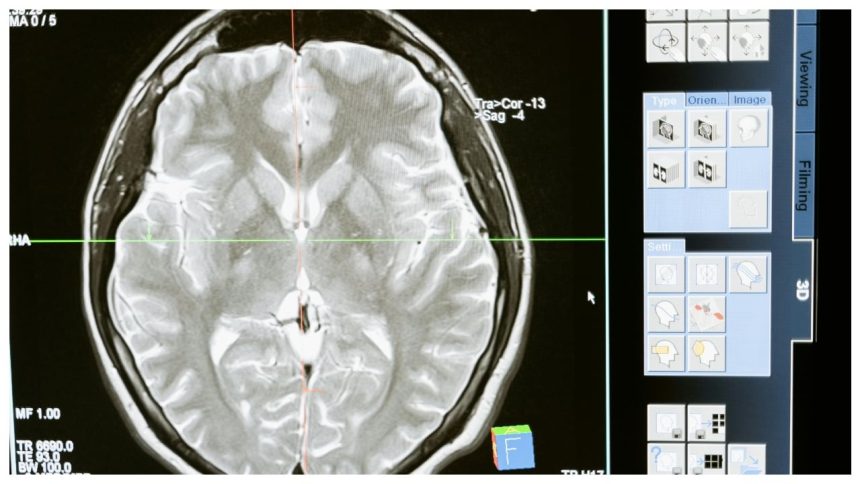

Stroke treatment

Thrombolytic are administered when the patient comes in an emergency to dissolve the clot and help the patient improve his/her quality of life. If the stroke is severe and blocks the major blood vessel in the brain then one will also require angioplasty and stents or even surgery. Moreover, one will also be recommended physiotherapy to move freely after the stroke. If the stroke affects the right side of the brain, movement and feeling on the left side of your body may be compromised. If the stroke damages the left side of the brain, movement and feeling on the right side of your body are known to be affected.